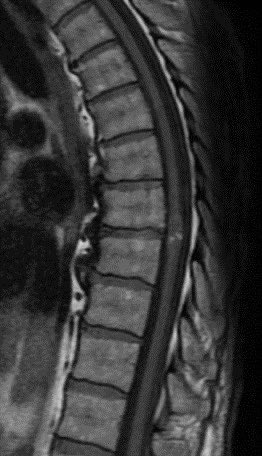

What is the most likely diagnosis in this 65 y/o M presenting w/ leg weakness, hyperreflexia, spasticity and absent vibration sense in the LE? #neu